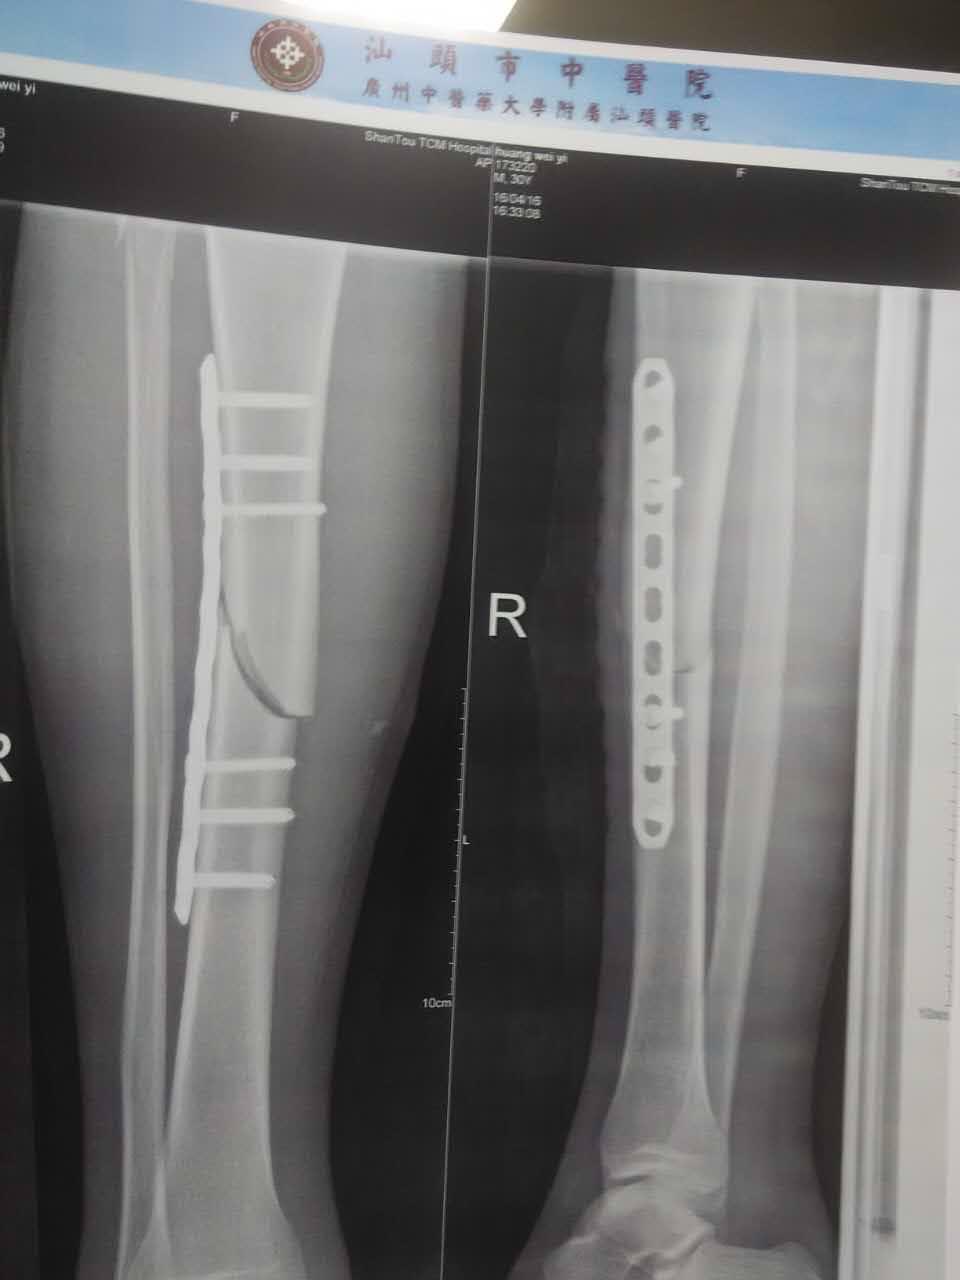

右胫腓骨远端骨折 医联